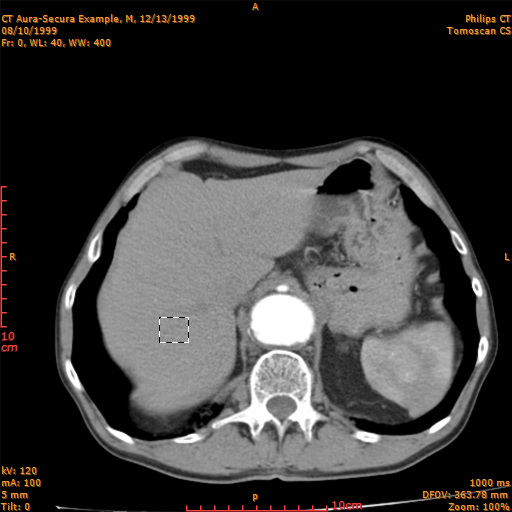

Rectangle:

The rectangle tool lets you select a rectangular area of your image.

In the examples is used the selection rectangle tool.